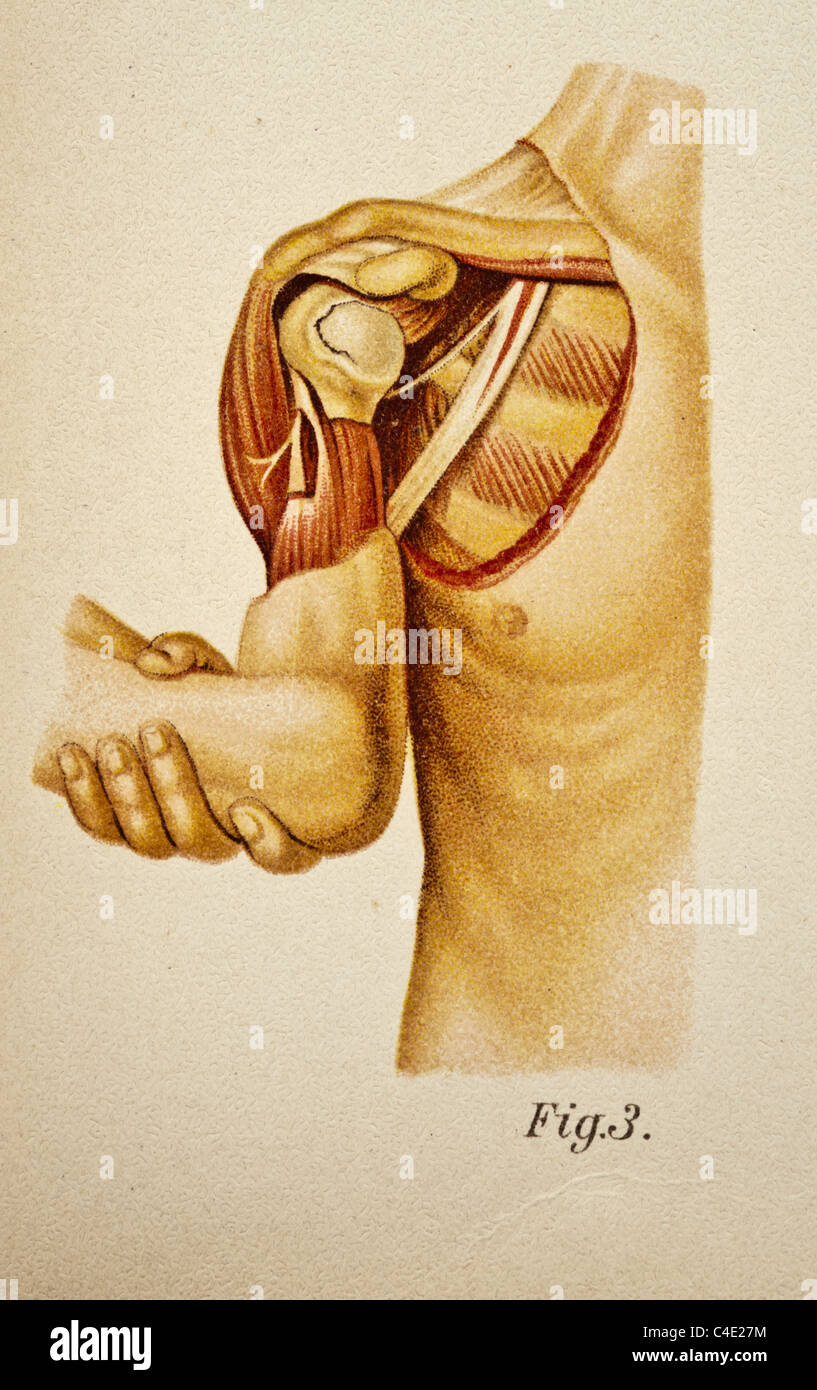

Illustration of the Human Shoulder copyright 1902 Stock Photohttps://www.alamy.com/image-license-details/?v=1https://www.alamy.com/stock-photo-illustration-of-the-human-shoulder-copyright-1902-37188472.html

Illustration of the Human Shoulder copyright 1902 Stock Photohttps://www.alamy.com/image-license-details/?v=1https://www.alamy.com/stock-photo-illustration-of-the-human-shoulder-copyright-1902-37188472.htmlRFC4E27M–Illustration of the Human Shoulder copyright 1902